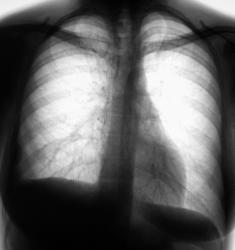

Сегодня произвели рентгенографию.